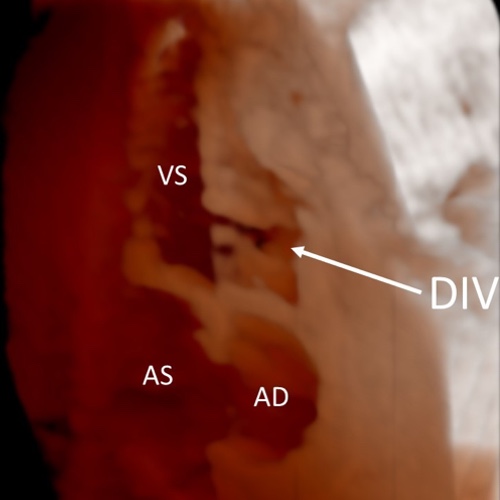

Ecocardiografia fetale 3D

Ecocardiografia fetale